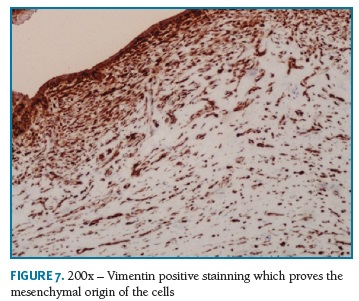

Definitive pathologic diagnosis of Pseudoangiomatous Stromal Hyperplasia (Fig. 4-5-6-7-8) was made on surgical specimen of mastectomy. The patient had regular follow-up at our department. Last visit was in May 2018, and no signs recurrence or contralateral breast cancer were diagnosed in those 11 years of follow-up.